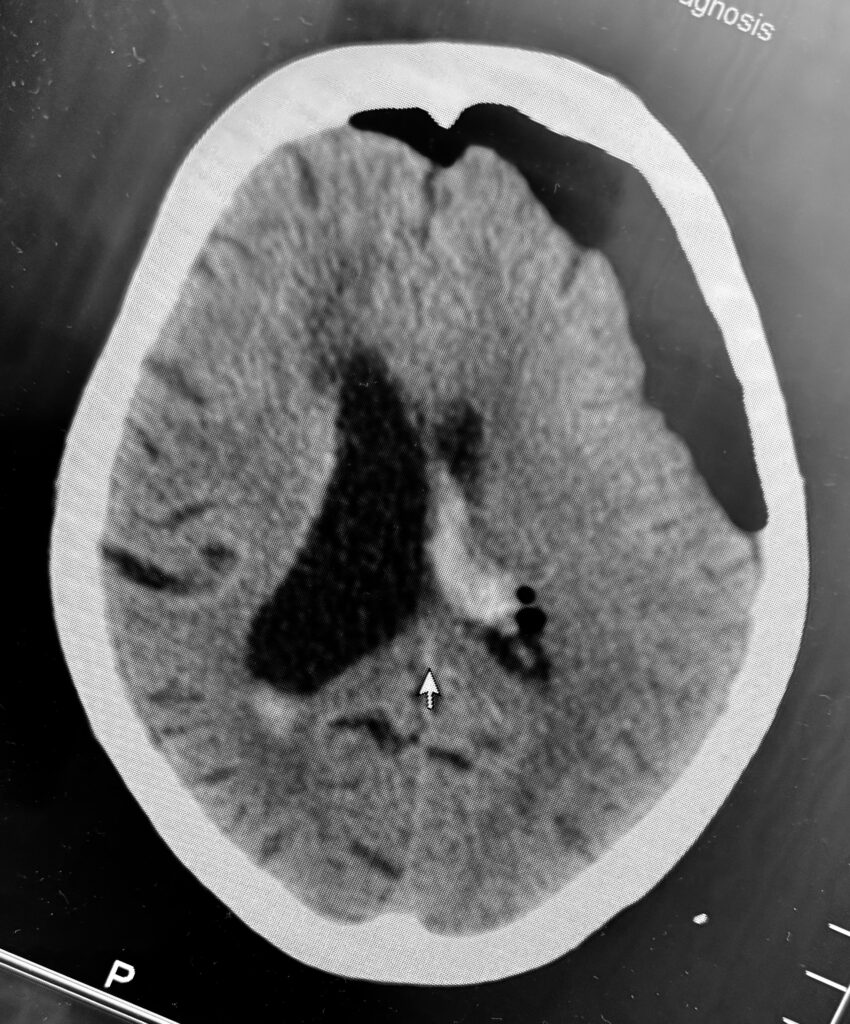

視床出血、脳室穿破の症例で、患者さんはご高齢なので内視鏡で低侵襲に血腫除去したいという要望でした。ご要望にお応えし、局所麻酔で3センチ切開し、1センチの穴を開けて血腫除去してきました。無事に血腫は取れたので今頃はリハビリテーションに励んでいることでしょう。

私は上記の写真のように個別にアプローチを決定し、透明シースを挿入し、内視鏡下に血腫除去する方法で良好な結果を得ています。ただし、エビデンスとなるとある程度の症例数を複数施設でまとめて、評価ポイントも決めて、別の治療方法との差を出して決まるので難しいです。